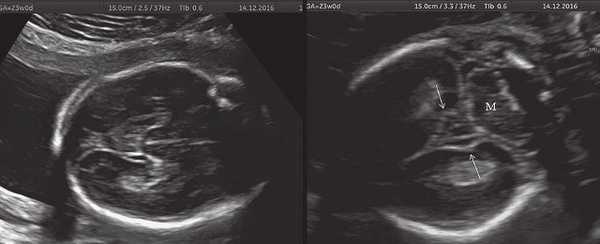

б) Беременность 23 нед. Нормальная картина нижнесагиттального и коронарного срезов нижней поверхности височных долей мозга плода. Стрелки указывают на наличие единственных шпорных борозд на коронарном срезе. М - можечок.